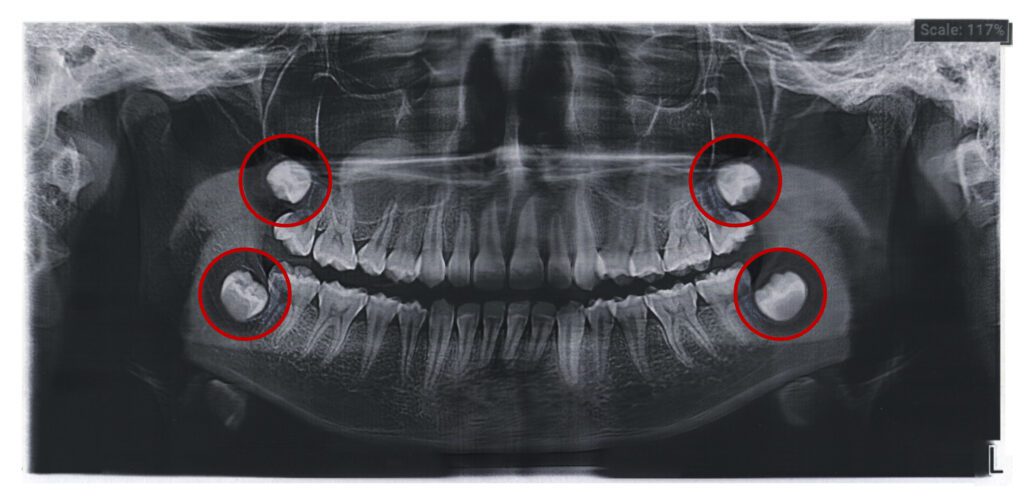

- Impaction: Wisdom teeth are impacted when they are blocked from erupting properly, either by other teeth or because the jaw does not have enough space.

Our expert team at Pure Gold Professionals in Dentistry will help determine whether your wisdom teeth are likely to cause problems based on X-rays and a comprehensive examination of your mouth. For those who have enough room and properly aligned wisdom teeth, removal might not be necessary, and regular monitoring will be recommended.

- Consultation and Evaluation: Your experience begins with a detailed consultation, where we discuss your dental health, take necessary X-rays, and evaluate the position and health of your wisdom teeth. This assessment helps us understand whether wisdom tooth removal is the best course of action for you.

- Advanced Technology: We use advanced imaging technology to accurately assess the position and condition of your wisdom teeth, leading to precise and effective removal.